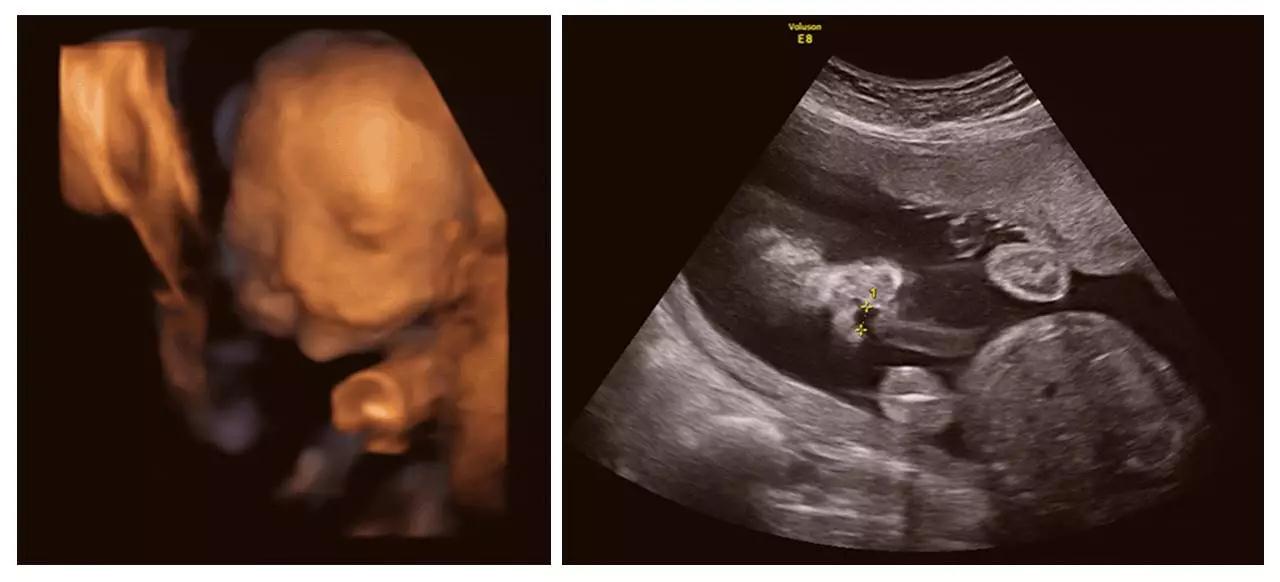

美GE不仅能提供包括腹部、血管、小器官、产科、妇科、泌尿科、新生儿和儿科等多领域的多方面的应用,而且能够显示未出生的宝宝的实时动态活动图像,为胎儿进行宫内拍“写真”和动态录像,让宝宝拥有完整的0岁相册。通过四维彩超(四维彩超),可以看到宫内胎儿打哈欠、伸懒腰、吮手指等萌萌的动作,让准爸妈们增添了安心和乐趣,不再仅仅是感觉宝宝的呼吸和运动,可以亲眼目睹宝宝的举动和乖巧容颜。还可以打印宫内高清写真,作为送给未来宝宝的珍贵礼物!

(单侧唇裂)

(双侧唇裂)